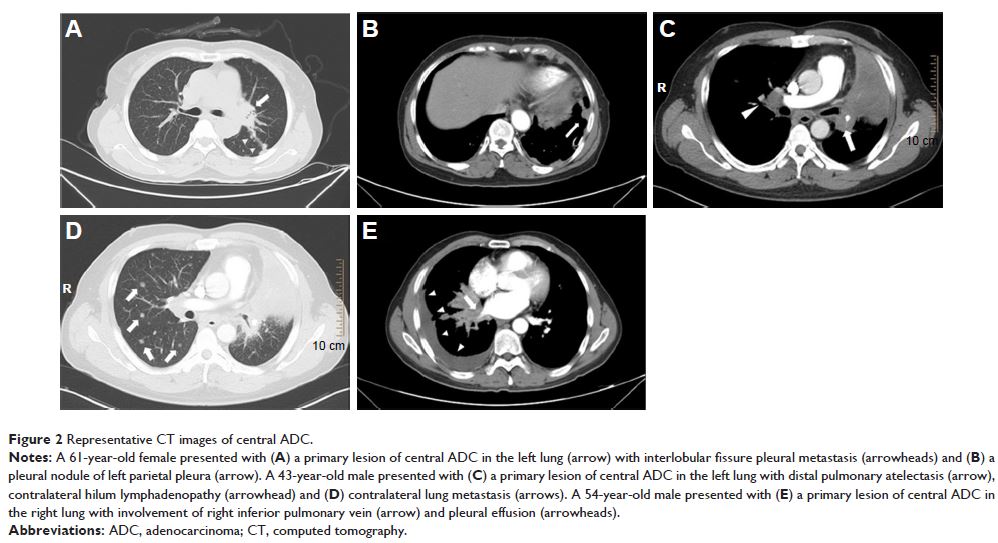

- 作者:Bin Liu, Zhenjie Wu, Hao Mo, Juliang He, Xiang Lin, Jian Guan, Changyuan Wei, Zhenchao Yuan

- 期刊:Cancer Management and Research